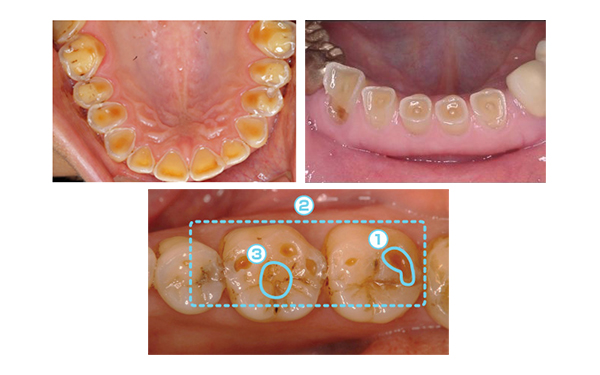

牙齒的酸蝕癥是怎么回事?

酸蝕癥是因飲食習(xí)慣,身體狀況等各種原因一起造成的牙體缺損現(xiàn)象。主要原因是食用酸性飲料、食物,慢慢酸化牙齒表面,造成牙齒缺損。進(jìn)一步發(fā)展下去,就會(huì)發(fā)展成蛀牙,牙本質(zhì)過敏等現(xiàn)象。

一旦得了酸蝕癥,牙齒情況不會(huì)恢復(fù)。不治療的話甚至?xí)绊懷例X咬合關(guān)系、傷害神經(jīng),和蛀牙一樣嚴(yán)重。

酸蝕癥患者根據(jù)癥狀嚴(yán)重程度不同,治療方式也不同。如果牙本質(zhì)為輕度傷害的話,可以涂藥液緩解癥狀;有牙本質(zhì)缺損的話可以進(jìn)行樹脂充填、冠修復(fù)等;如果已影響牙神經(jīng)的話要去神經(jīng),進(jìn)行根管治療。